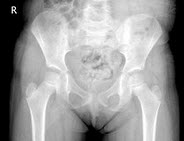

34、单项选择题

女,根据其正常骨盆影像图像,判断其最可能的年龄()

A.2岁左右

B.5岁左右

C.8岁左右

D.11岁左右

E.14岁左右

点击查看答案